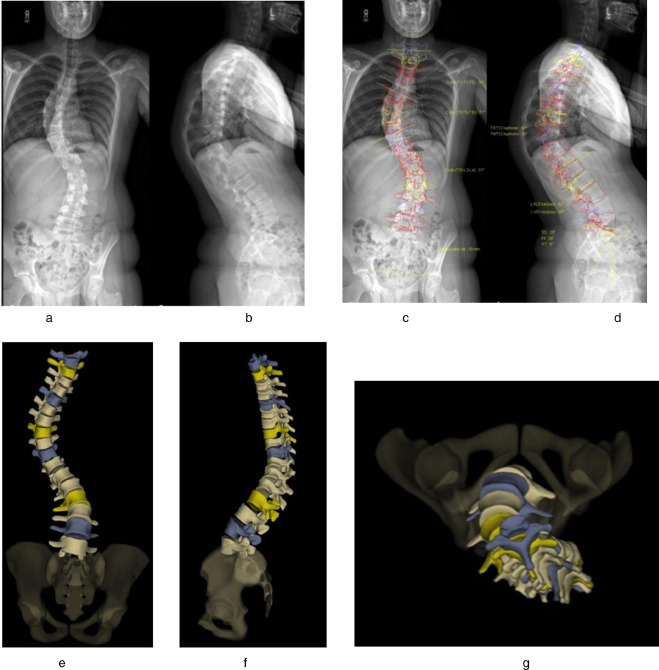

این فناوری نوین از پیشرفته‌ترین سیستم‌های تصویربرداری اسکلتی ـ عضلانی در سطح جهان به شمار می‌رود و امکان تهیه هم‌زمان تصاویر از نماهای قدامی و جانبی بدن را در وضعیت ایستاده و طبیعی فراهم می‌کند.

سیستم EOS قابلیت بازسازی سه‌بعدی دقیق ساختار اسکلتی بدن را داراست و نقش مهمی در تشخیص و پایش ناهنجاری‌هایی همچون اسکولیوز، اختلالات قامتی، اختلاف طول اندام‌ها و نیز برنامه‌ریزی پیش و پس از جراحی‌های ارتوپدی ایفا می‌کند.